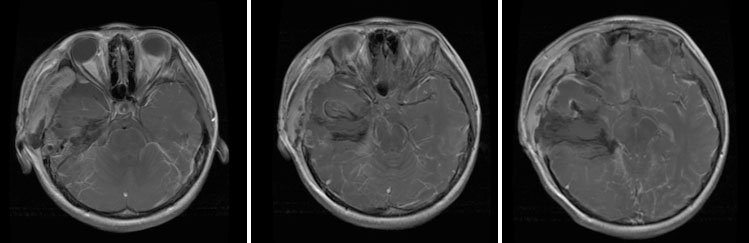

(3)

手术全切肿瘤

术后短期内(3周)迅速复发